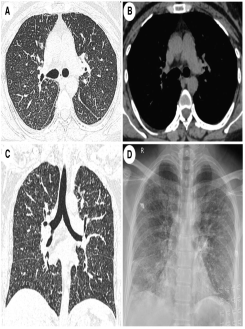

彭红团队报道了一例罕见突变所致肺泡微石症病例

近日,中南大学湘雅二医院呼吸与危重症医学科间质性肺疾病亚专科学术带头人彭红教授团队在国际权威杂志《An International Journal of Medicine》(QJM,IF= 13.3)在线刊发了题为《A novel compound heterozygous mutation in the SLC34A2 gene causes pulmonary alveolar microlithiasis》的论文。中南大学湘雅二医院为第一单位和通讯单位,中南大学湘雅二医院呼吸与危重症医学科刘青清主治医师为第一作者。该研究报道了一例因SLC34A2杂合突变导致不典型肺泡微石症的罕见患者。

肺泡微石症是一种罕见肺间质疾病,以肺泡内弥漫性沉积的含钙、磷盐为主的微小结石导致肺功能进行性损害为主要临床表现,主要治疗方式为肺移植。SLC34A2基因编码磷酸钠协同转运蛋白,该蛋白在Ⅱ型肺泡上皮细胞中表达量很高并且参与体内无机磷代谢。

本报道通过全外显子测序在一例不典型肺泡微石症的患者中检测出新的SLC34A2突变位点,患者父母双方各自携带该基因突变造成该患者为复合杂合突变最终出现临床表型,患者就诊时因肺部病变较轻,对症治疗后症状控制尚可。

原文链接:https://academic.oup.com/qjmed/article/117/4/293/7468130?login=true